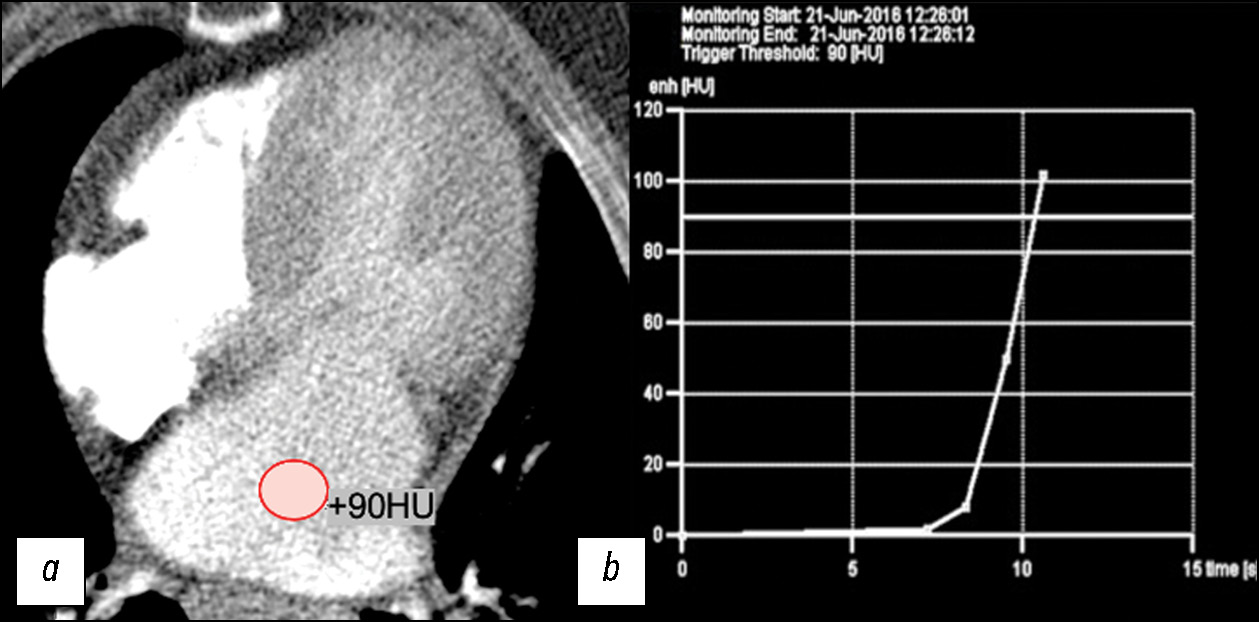

MATERIALS AND METHODS: The retrospective data analysis included 47 patients with hypertrophic cardiomyopathy (mean age, 52±7 full years) before surgical correction. computed tomography was performed using our protocol with automatic bolus tracking in the left atrium with a 90 HU threshold and biphasic contrast injection to assess the heart chambers and coronary arteries anatomy and mitral valve morphology. Moreover, to assess myocardial structure remodeling, iodine dual-energy computed tomography maps obtained with delayed contrast enhancement were analyzed. All patients with hypertrophic cardiomyopathy were classified by morphological types. The anatomy of chordopapillary apparatus was evaluated in each case.

RESULTS: This study demonstrated variability in hypertrophic cardiomyopathy phenotypes, which were conventionally divided into five morphological categories, but not restricted by them. Among the patients, 26 (55%) had diffuse septum hypertrophic cardiomyopathy, 5 (11%) had midventricular hypertrophic cardiomyopathy, 2 (4%) had midventricular obstruction and apical aneurysm, 8 (18%) had focal basal septum hypertrophic cardiomyopathy, 4 (8%) had concentric hypertrophic cardiomyopathy, and the remaining 4 (8%) had apical hypertrophic cardiomyopathy. Most patients were diagnosed with chordopapillary abnormalities of the mitral valve, categorized by papillary muscle number and position, and the ratio of chords to muscles. In 10 (21%) patients, data on the myocardial bridge of a coronary artery were obtained, whereas 3 (14%) of them had dynamic stenosis. All patients had focal iodine uptake on dual-energy computed tomography maps. An extracellular volume increase was observed in 10 out of 13 (76%) patients. As shown by dual-energy computed tomography, the mean extracellular volume of the left ventricular myocardium was 30.58% (95% confidence interval, 27–34%).

CONCLUSION: Our scanning protocols developed with computed tomography scanners of various generations enable to evaluate the specific morphological patterns of hypertrophic cardiomyopathy in a single study and provide a detailed interpretation of the geometry of cardiac valves and chambers, left ventricular function, state of the coronary bed, and structural changes of the left ventricular myocardium.